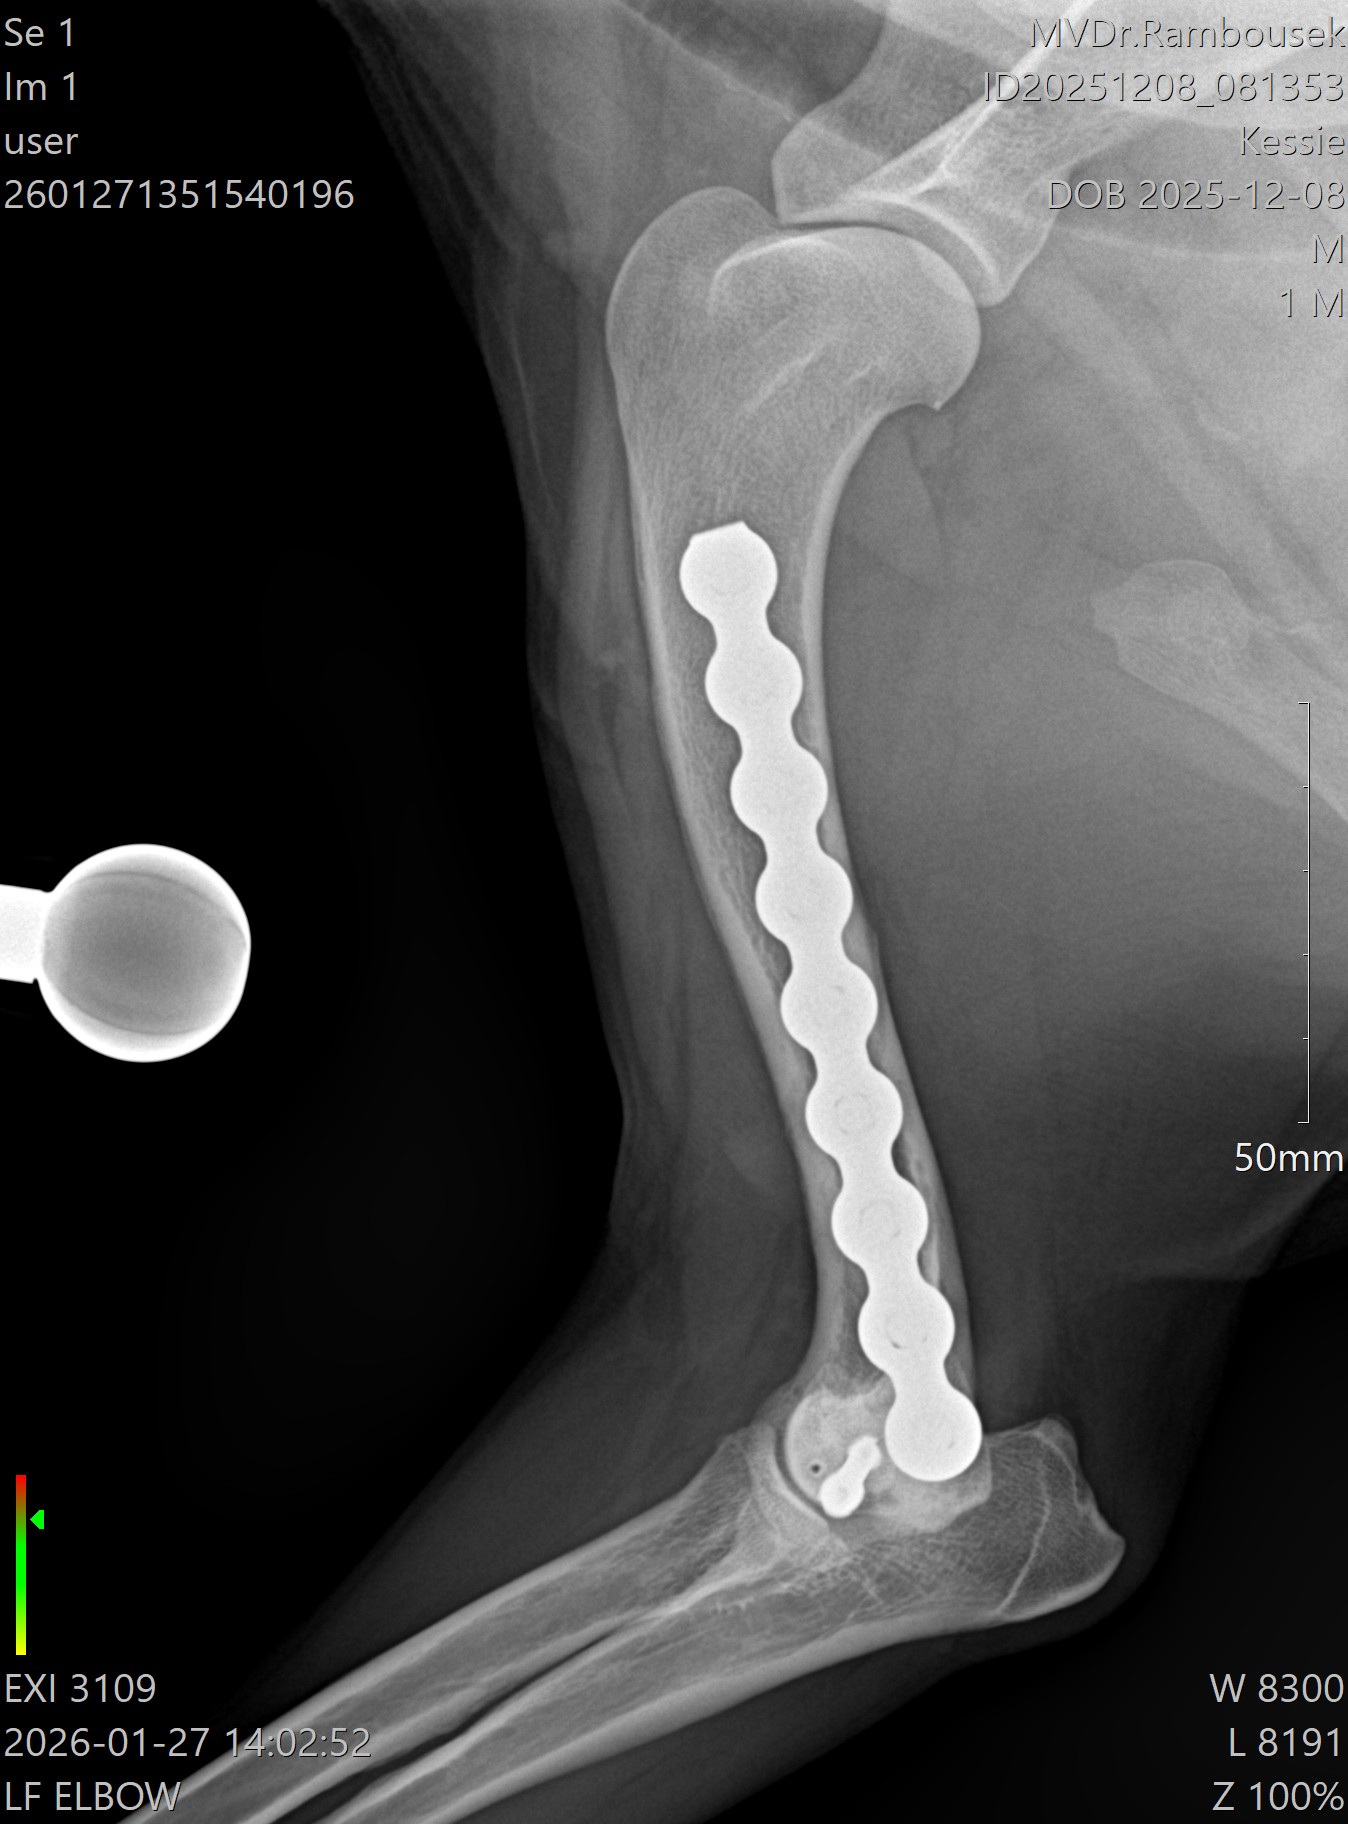

Fraktura pažní kosti - mediální kondylus

Případy z praxe

Akutní

případ